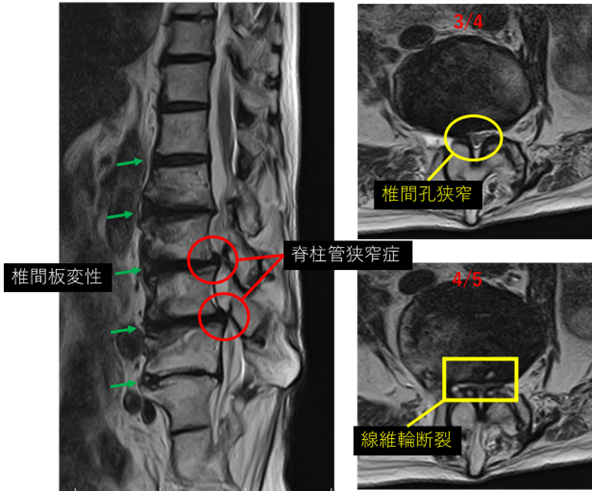

画像及び所見について

L1/2: 椎間板変性

L2/3: 椎間板変性、減高

L3/4: 椎間板変性、減高、膨隆、脊柱管狭窄症

L4/5: 椎間板変性、膨隆、減高、脊柱管狭窄症、線維輪断裂

L5/S: 椎間板変性、減高、膨隆

以上の事が画像上認められます。

L3/4、4/5 に

椎間板変性、脊柱管狭窄症、線維輪断裂 を認め、主症状の原因の可能性が高い。